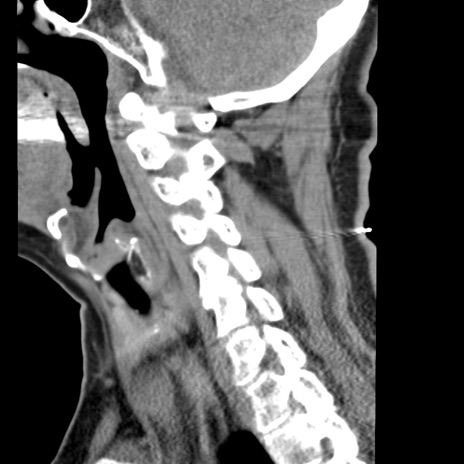

症例50 頚椎CT(矢状断像)

【症例】60歳代女性

【主訴】後頭部〜右後頸部にかけての痛み

【現病歴】本日飲食店でコーヒーを飲んでいたところ、突然後頭部〜右後頸部にかけて痛みが出現し、右上肢の感覚障害を伴ったため救急要請。

【身体所見】脳神経学的に明らかな異常所見を認めず。右上肢に軽度の感覚障害あり。

異常所見と診断は?

頚椎CT